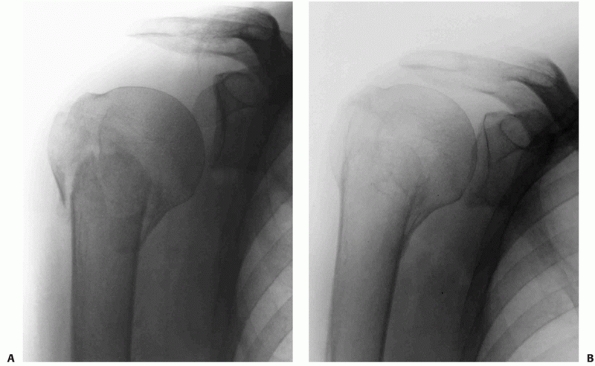

FIGURE 35-9 A,B.

Undisplaced and stable fracture configurations are best treated nonoperatively in most elderly patients, as shown in these two examples. |